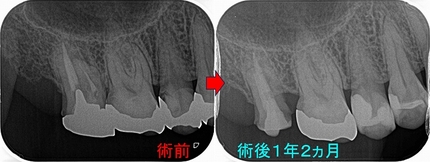

術式の差による骨の治り

たまにある側切歯の大きな病変(レントゲンのこの黒い部分は細菌由来の炎症で骨がありません)

2026 EEdental INA (1).jpg

意外と側切歯の根尖病変は大きくなりやすいのと、前歯の中で予後が最も悪い歯なので

前歯を残したい方は神経の治療は歯内療法専門医に任せた方がいいと思います。

以前の治療で根管内を太く削ってあったので外科的歯内療法を選択しました。

2026 EEdental INA (2).jpg

だいぶ大きく骨が無くなっておりスルー&スルー(唇側から裏側までトンネル状に骨がない)の状態でした。

こうなると骨が治る足場が無く骨の治りは遅くなります。

2年予後

2026 EEdental INA (3).jpg

スルー&スルーで貫通した部分にはまだ透過像があります。。。

ただ、膿や腫れはなく経過は良好です。